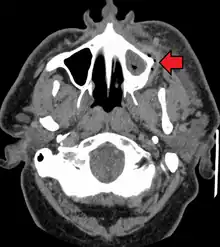

A dental infection resulting in an abscess and inflammation of the maxillary sinus

CT scan showing a large tooth abscess (right in the image) with significant inflammation of fatty tissue under the skin

If left untreated, a severe tooth abscess may become large enough to perforate bone and extend into the soft tissue eventually becoming osteomyelitis and cellulitis respectively. From there it follows the path of least resistance and may spread either internally or externally. The path of the infection is influenced by such things as the location of the infected tooth and the thickness of the bone, muscle and fascia attachments.